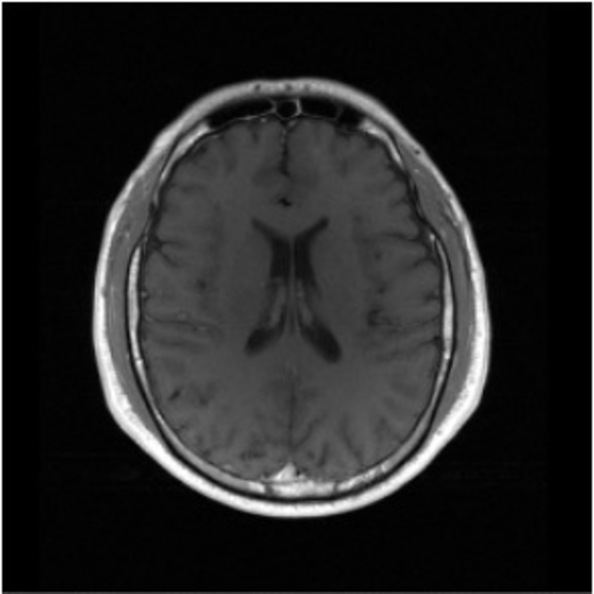

Figure 2: Example MRI magnitude reconstructions with S=25S=25 training slices at acceleration factor R=7R=7. PaDIS-MRI reconstructions are sharper and more faithful to the fully-sampled ground truth. Insets are shown to highlight detail.

Figure 2 provides a visual comparison of the reconstruction quality of each method on example slices. In reconstructions from the S=25,R=7S=25,R=7 models, FastMRI-EDM exhibits slightly more blurring and loss of fine structural details, particularly in regions with complex anatomical features. PaDIS-MRI, in contrast, preserves sharper boundaries and finer details. This enhanced data efficiency can be attributed to the patch-based prior’s ability to learn localized structural motifs more effectively from limited examples. Figure 6 in the Appendix shows similar reconstructions at S=200,R=7S=200,R=7 where FastMRI-EDM more closely approaches the performance of PaDIS-MRI but still struggles with highly detailed anatomy. At both dataset sizes, MoDL underperforms the diffusion priors. In Figure 2, MoDL’s FLAIR reconstruction exhibits pronounced artifacts, likely reflecting reduced generalizability of a supervised prior when the training distribution underrepresents FLAIR.